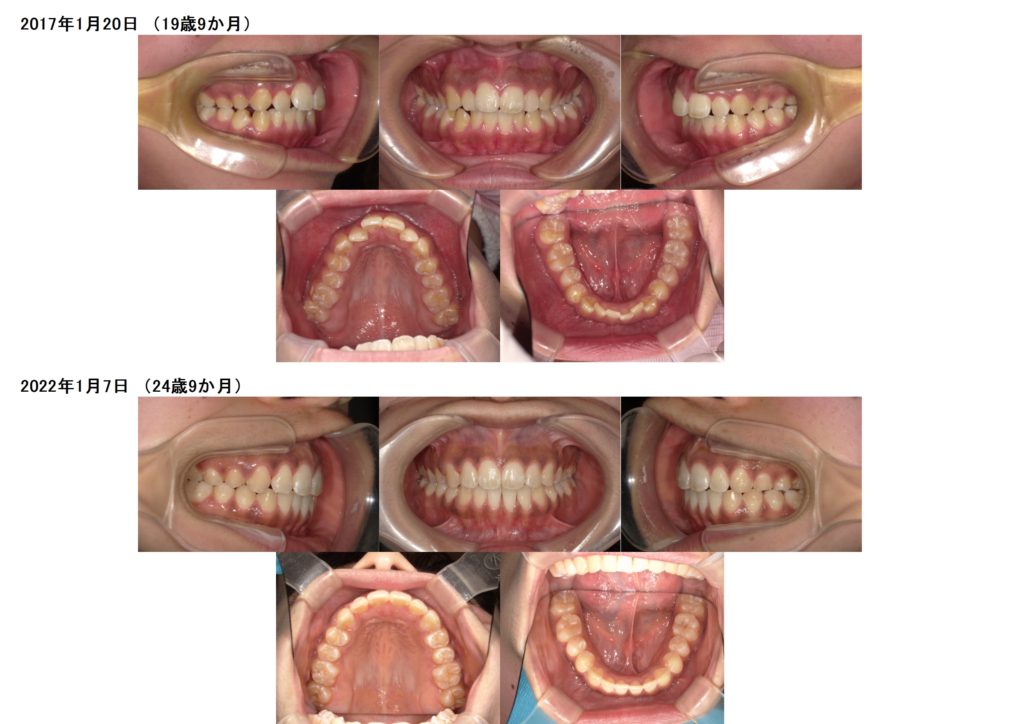

今回は、叢生(ガタガタ歯並び)、噛み合わせの治療をマウスピース、アライナーを使用した治療例になります。

上下の写真を見比べてみると上下の顎の土台をしっかりと整ったのが分かると思います。

特に、上のアーチの形が変わったのが分かりますよね☆

このように、少しずつの変化ですが、マウスピースでもどんな歯並びの方でも可能です。

しっかりと噛み合わせを重視し、奥歯から全体の歯をしっかり動かし、歯並びを並べていくと、後戻りのリスクも減らせますし、土台の変化をする事が出来るのでお口の中もとてもきれいに整います。

全体を歯を動かす治療は、土台の形を骨格に一番適した数値にしたり、噛み合わせの治療をする事により、歯並びもキレイに並びます。

歯並びだけをキレイにする治療ではありませんので、その分治療期間もかかってきますが、噛み合わせを治さないと後々、噛むことが出来ない、といった不具合も出てくる可能性がありますので、しっかりとカウンセリングを受けてから治療を開始することをおススメします。